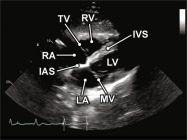

| 2.14. Mặt cắt 4 buồng từ mỏm |

||||||||

|

|

Cửa sổ siêu âm từ mỏm tim Mặt cắt 4 buồng

Bệnh nhân nằm nghiêng trái, xác định diện đập của mỏm tim, marker đầu dò hướng về giường bệnh |

Nhĩ trái (LA)

Van hai lá (MV) Thất trái (LV) Vách liên thất (IVS) Thất phải (RV) Van ba lá (TV) Nhĩ phải (RA) Vách liên nhĩ (IAS) |